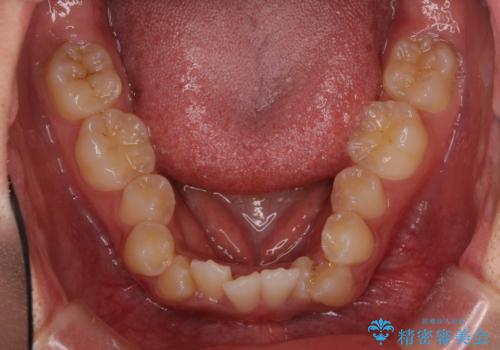

著しい八重歯が気になる インビザラインでの矯正治療

- 顕著な八重歯が気になるとのことで来院された患者様です。

インビザラインでの治療を希望されましたが、インビザライン単独では困難と判断されたため、補助装置や一部ワイヤー装置を用いて行うこととしました。

叢生が強いため、上下左右第一小臼歯4本を抜歯することとしました。